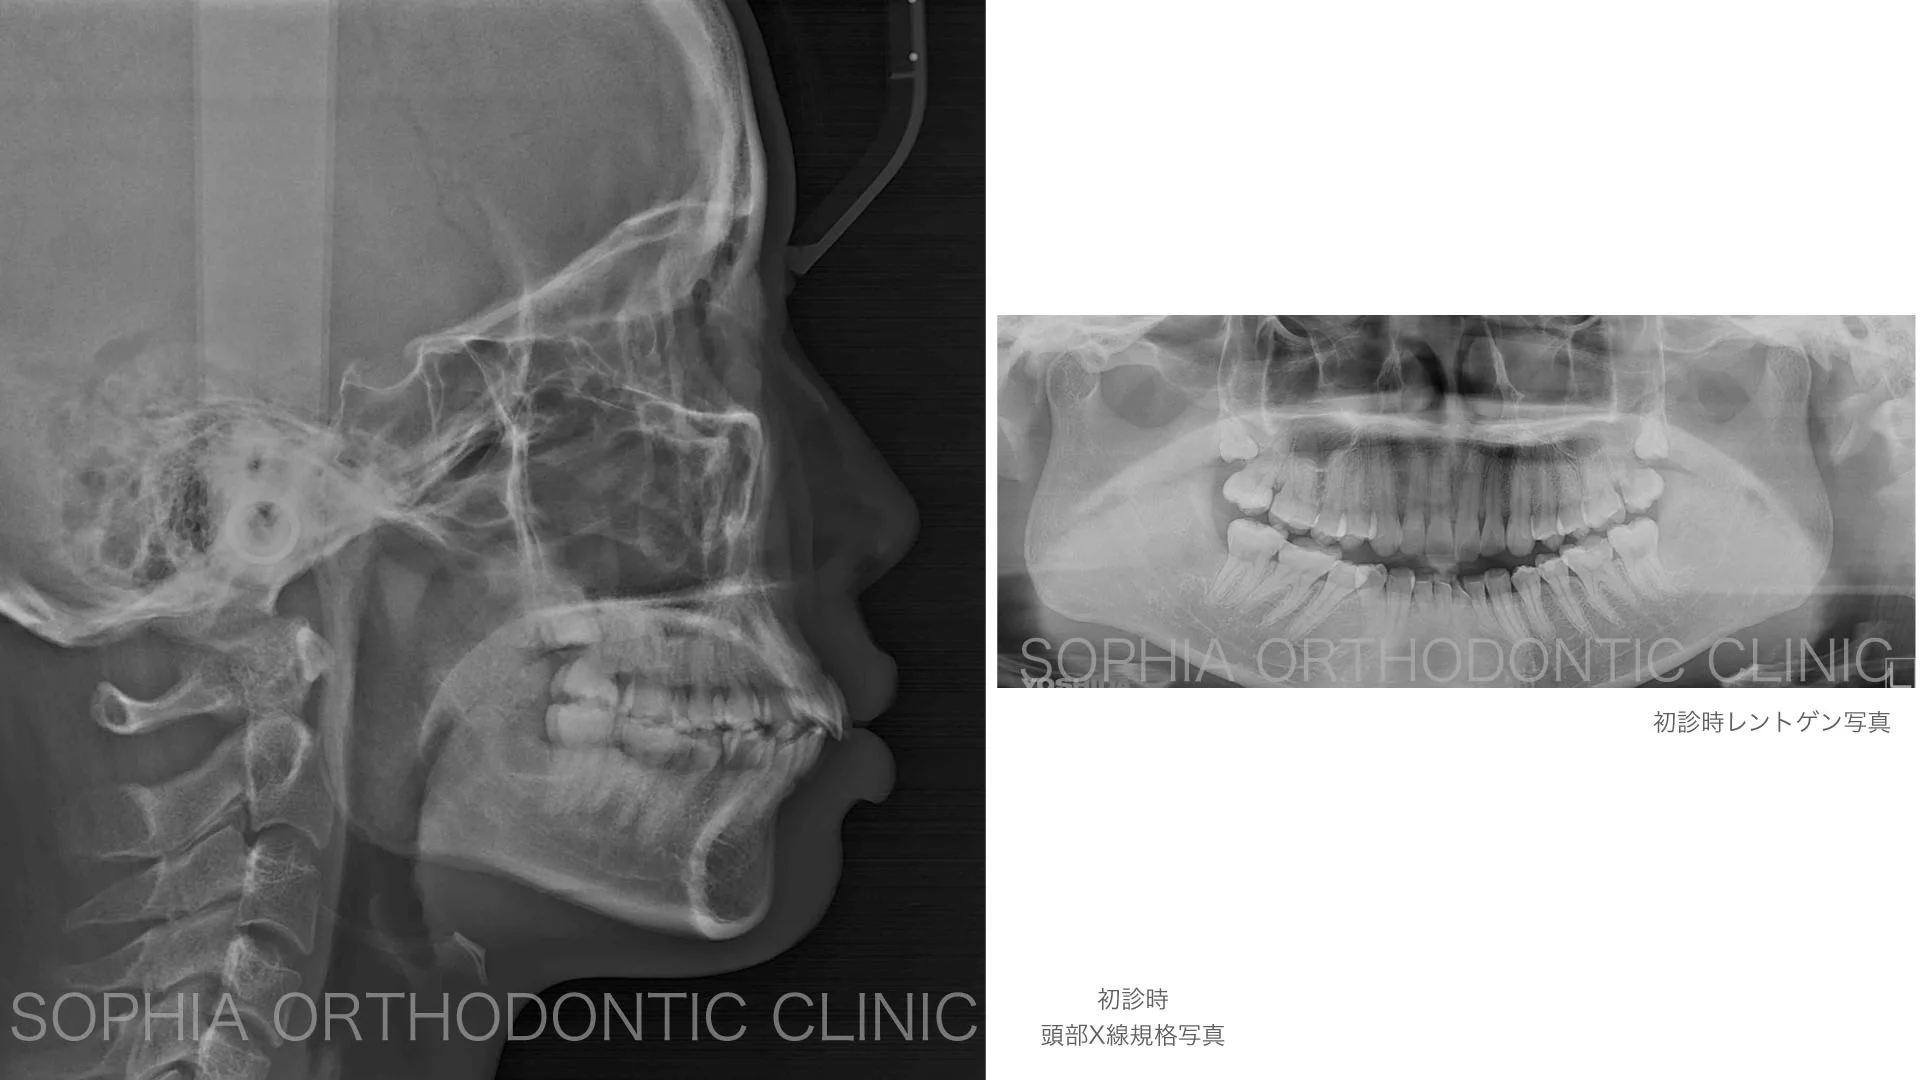

症例 前突